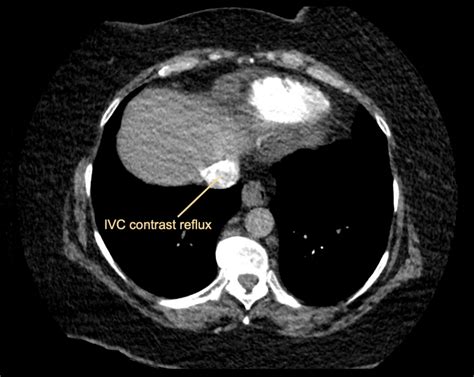

TitleCT Case 009 • LITFL • CT scan interpretation